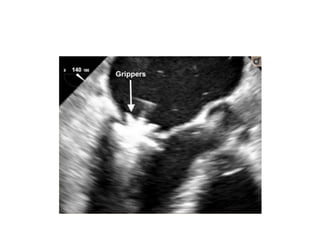

• After grasping of the leaflets, leaflet capture is evaluated by lowering the

gripper and partially closing the clip to secure leaflet insertion.

Grasping of theleaflets, assessment of the result and clip release • Once the MitraClip is in a satisfactory position, grasping of the leaflets using a 2D LVOT view. • It is recommended to do this with the help of a short breath-hold, controlled by the accompanying anaesthetist. • Multiple planes are useful for assessment of proper leaflet insertion into the MitraClip. • The insertion of the posterior leaflet is commonly best seen in the LVOT view, and the insertion of the anterior leaflet in the four-chamber view. • The intercommissural view can add information such as entrapped chordae tendinae. • After grasping of the leaflets, leaflet capture is evaluated by lowering the gripper and partially closing the clip to secure leaflet insertion. • Formation of the double-barrelled orifice is confirmed with an en face view to make sure that each orifice is approximately the same size.

• #30 After grasping of the leaflets, leaflet capture is evaluated by lowering the gripper and partially closing the clip to secure leaflet insertion